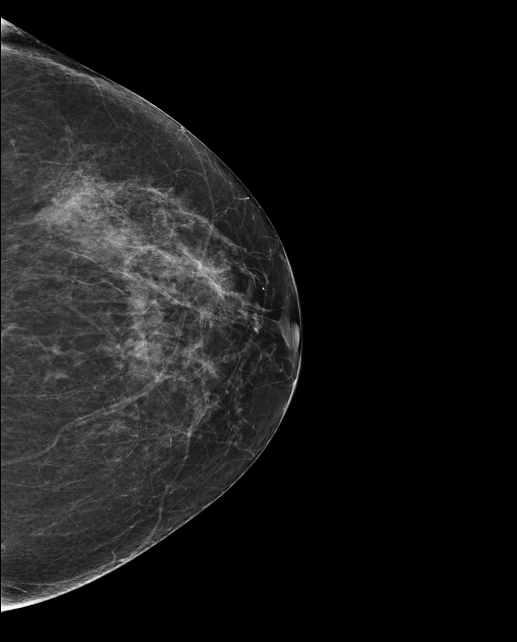

Mammographie de dépistage, patiente de 73 ans.

Antécédent néoplasie mammaire mère et tante maternelle.

Apparition d’une masse supéro-interne de 6mm à 9 cm du mamelon aux contours circonscrits, taguée suspecte par MammoScreen.

L’échographie révèle une lésion ronde hypoéchogène mal limitée avec halo périphérique hyperéchogène de 6mm de rayon.

3 microbiopsies sous guidage éco sont réalisées, un clip est posé.

Biopsie positive cancer.